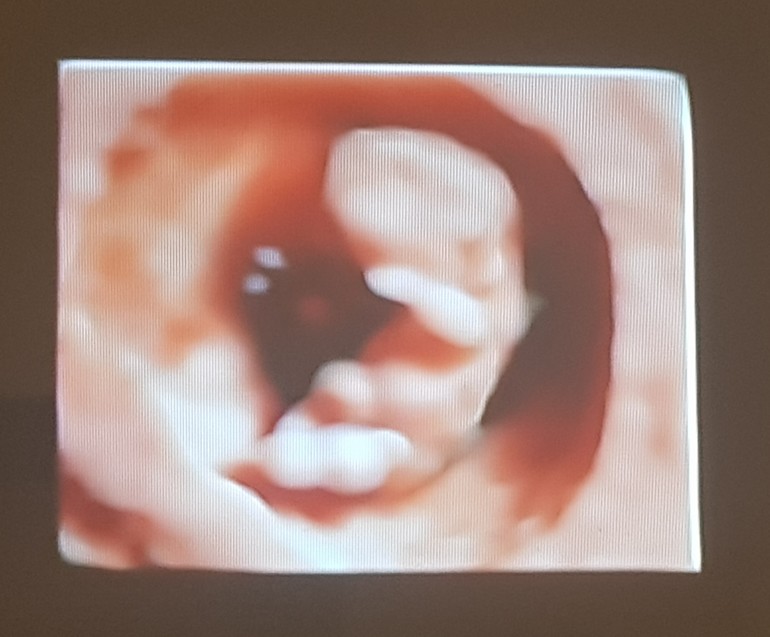

УЗИ 10+1 и НИПТ (фото 3D)

КТР 31,7 мм

Сердечко стучит быстро - 171 уд/мин.

Включили 3D режим - прямо вау)))